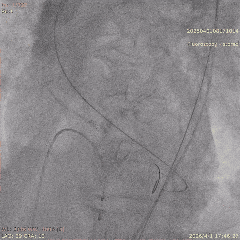

手术当天,团队顺利完成经导管主动脉瓣置换术。术中瓣膜释放位置理想,人工瓣膜功能良好,未见明显瓣周漏,也未出现严重传导阻滞、恶性心律失常等情况,患者术后安返CCU病房。

▲导丝跨瓣

▲18mm球囊预扩

▲输送器过弓

▲瓣膜定位

▲释放至工作位

▲工作位造影

▲脱钩

▲20mm球囊后扩

▲最终造影